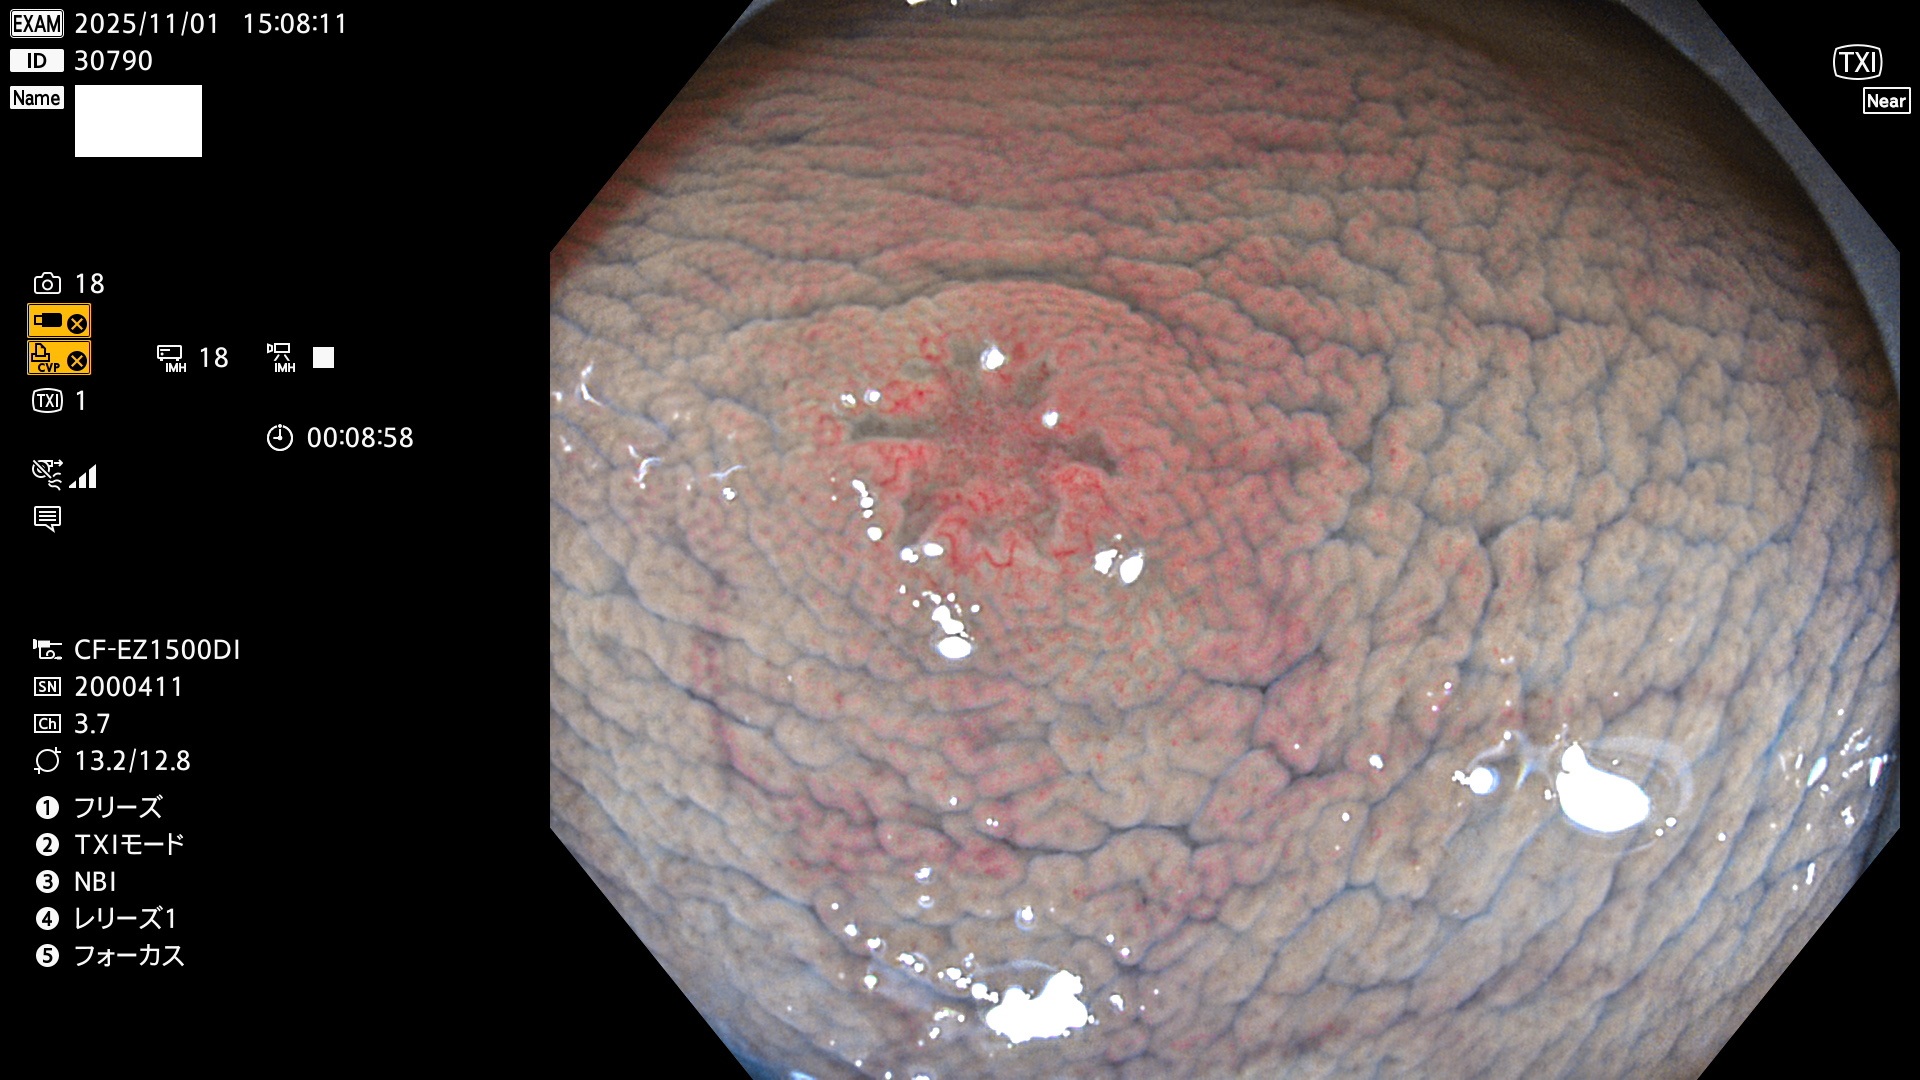

完全に平坦な物をUb、陥凹している物をUcと呼びます。Ubは認識が困難で、Ucはびらん(炎症)と紛らわしいために見落とされやすく、「内視鏡後・大腸癌」の原因になります。

専門的)Uc=De Novo癌? 内視鏡の解像度が低かった時代、このような説もありました。しかし今日の高精度内視鏡では良性の微小なUc型腺腫(APC遺伝子異常の腺腫)が日常的に見つかります。Ucこそが多段階発癌(Adenoma-Carcinoma Sequence)のMain Routeです。

毎週の検査(木・金・土・日)に発見されたUbとUc型・腺腫を、その週の日曜の夜にUPし1週間、提示します。

2025年10月30日〜11月2日の4日間(40件)9個 (Uc_ADR=9個/40人=23%)